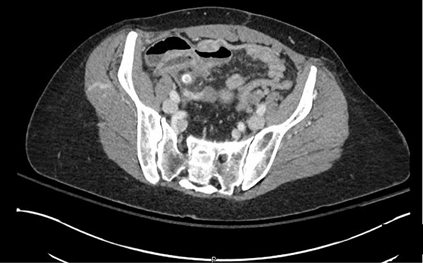

A 48 year old female with a history of a previous cesarean section and lower abdominal ventral hernia (Figure 1) underwent abdominal wall reconstruction with component separation including external oblique release, intra-abdominal placement of Strattice acellular dermal matrix with Prolene transfascial sutures, and direct midline closure with permanent sutures of prolene and rectus muscle plication with permanent prolene sutures. The patient had an uneventful postoperative course and at six weeks returned to unrestricted physical activity without limitations. A postoperative CT-scan obtained several months later demonstrated a well repaired ventral hernia with approximation of the rectus muscles as well as the visible presence of the Strattice acellular dermal matrix in the underlay position (Figure 2).

Figure 1 Pre-operative CT scan showing midline umbilical and ventral hernia as well as rectus diastasis.